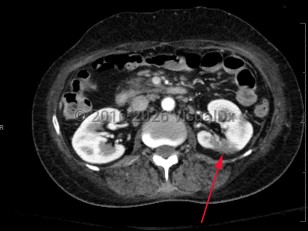

Renal infarctionRenal infarction

Renal vein thrombosis

Perinephric abscessPerinephric abscess

Renal nutcracker syndrome

Ureteral calculus